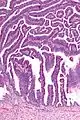

| Micrograph of a villoglandular adenocarcinoma the cervix. H&E stain. | |

The name of the lesion describes it microscopic appearance. It has nipple-like structures with fibrovascular cores (papillae) that are long in relation to their width (villus-like), which are covered with a glandular pseudostratified columnar epithelium.

Very low magnification